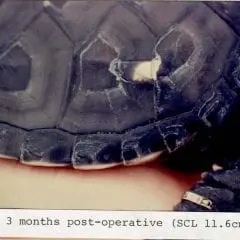

2012- Photo Depictions of Auto-Grafting a Juvenile Green Turtle.